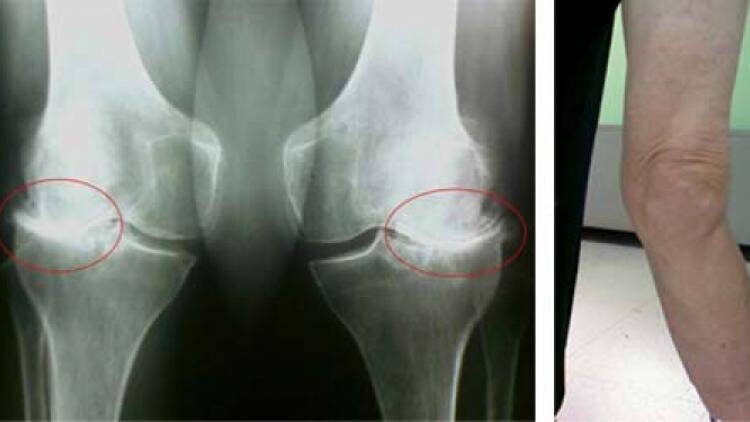

• Появились уплотнения или деформация.

Диагностика за 1 день:

1. Рентген или МРТ.